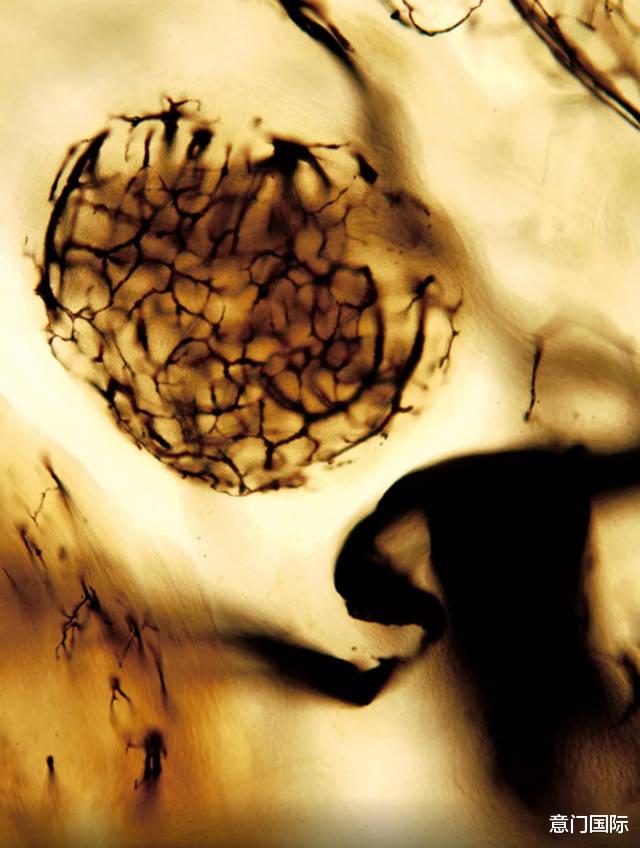

李铁军教授是国际口腔病理学领域的权威学者,数十年来致力于推动学科发展。而本次展览则揭示了他专业成就之外的另一重身份——一位用科学之眼捕捉生命之美的艺术家。他的创作将牙科显微镜下的生物结构,转化为一幅幅令人惊叹的视觉构图,淋漓尽致地展现了隐藏在牙齿与组织中的、精微绝伦的天然秩序与美学。

在随后于PPDH演讲厅举行的学术交流会上,李教授与听众分享了他的创作心路。他谈到:“艺术追求美;科学追求真理。” 正是这种对科学数十年的执着钻研与对美学的终生迷恋,共同催生了他独特的艺术视角。在他的镜头下,科学样本超越了其研究价值,升华为充满诗意的艺术杰作。

“每个细胞都会讲故事,每个分子都会创造奇迹,” 李教授阐述其创作哲学时指出,“这些影像本身不是像艺术,它们只是给了一种新看法。” 他认为,这些微观图像的认知价值,既能通向一个更清晰、更精确的科学世界,也能延伸至一个更广阔、更混沌的艺术国度。

在可见与不可见、测量与感觉、经验与诗性之间,李铁军教授的作品构建了一种全新的语言。在这种语言中,医学与艺术、技术与传统不再彼此对立,而是相互启发,相得益彰。其作品的终极指向,是引领观者去聆听和凝视生命形式本身最原始、最动人的自然节奏。

摄影作品欣赏: